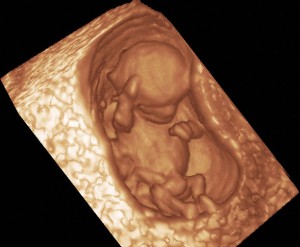

anne karnında bebek fotoları

4 haftalık bebek görüntüsü 25 haftalık bebek 25 görüntüsü

anne karnında 4 haftalık

anne karnında 4 haftalık